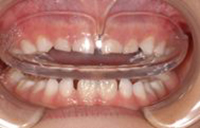

装着時

ムーシールドとは透明な小児用マウスピース型の矯正装置で、反対咬合(受け口)の治療に使用します。

乳歯側の反対咬合です。

歯列矯正用咬合誘導装置(ムーシールド)を5ヶ月間使用していただき、きれいに治りました。

| 初診時年齢・性別 | 4歳7ヶ月 男性 |

|---|---|

| 主訴 | 乳歯のかみ合わせが反対 |

| 診断名・主な症状 | 前歯部の反対咬合 下の顎が広がってきている |

| 治療内容 | 歯列矯正用咬合誘導装置(ムーシールド)を装着する事ができたので、 就寝時しっかり使って治療 |

| 治療期間 | 5ヶ月 |

| 注意点・リスクなど | 保護者による管理が必要、舌を正しい位置に置かないと改善しない |

| 治療費用 | 約13,000円 |